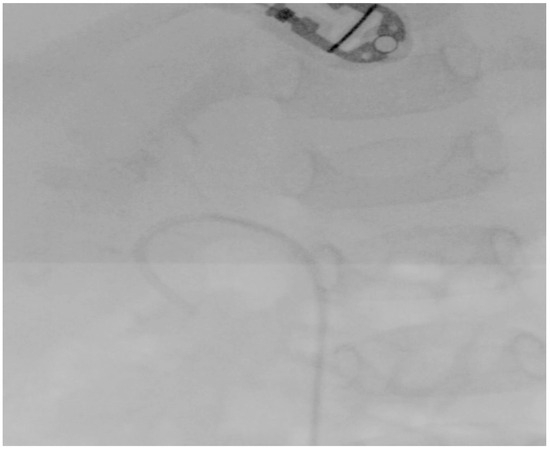

Two months later, a cystoscopy under general anesthesia was performed, followed by fluoroscopy of the right renal collecting system and the ureter. Fluoroscopy revealed the angle of the right ureteropelvic junction, while, after artificial dilation, the infundibulum of all the calyces seemed to be of adequate size for the maneuverability of the single-use flexible ureteroscope. Based on the preoperative non-contrast CT scan, the size of the lower calyx was 16.4 × 6.8 mm, and the infundibulopelvic angle was estimated to be 94.9°/265.1° (Figure 3). Consequently, based on the manufacturer characteristics of the single-use flexible ureteroscope utilized, the anatomy was convenient for the exploration of the whole calyx. It was then that the treatment plan was orientated towards fURSs. Finally, a 3.7 F/12 cm JJ stent was inserted.

Figure 3. The size of the lower calyx and the infundibulopelvic angle. They were measured preoperatively to provide significant information for surgical planning decisions.